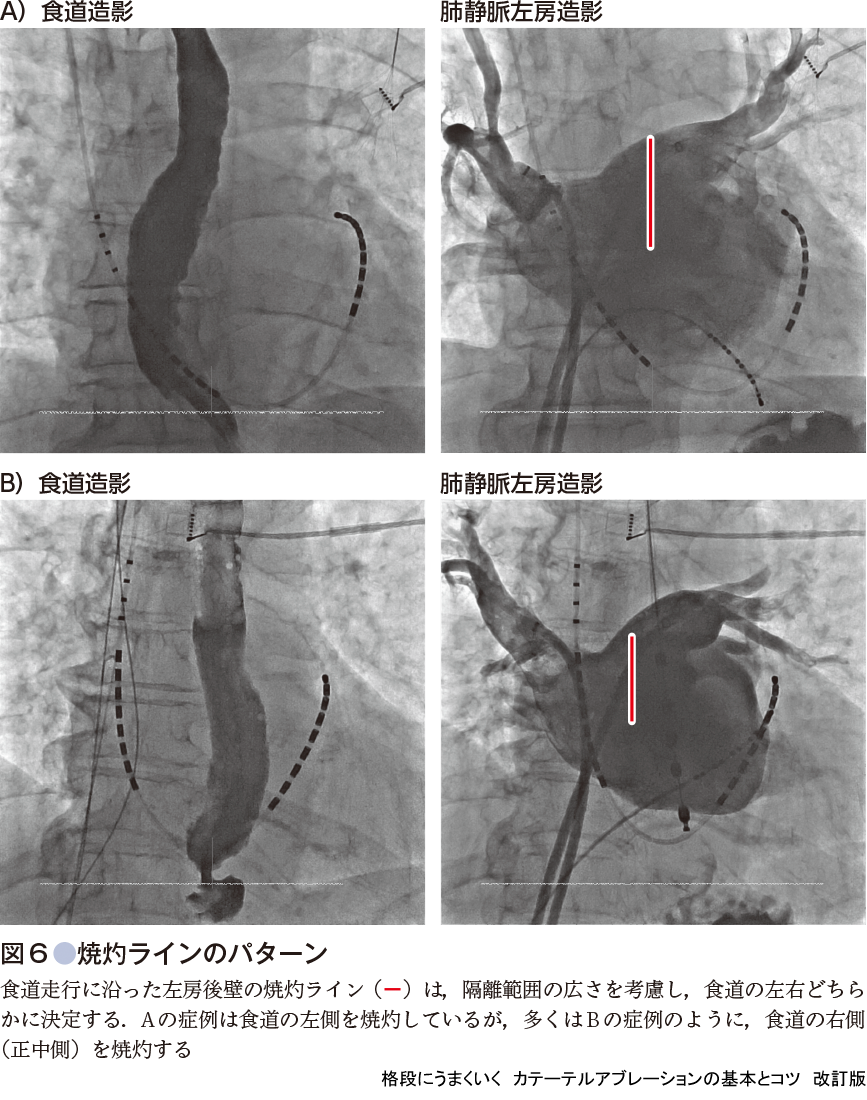

肺静脈隔離時に食道の走行に沿って,上下に左房後壁を焼灼する際は,食道上の左房後壁を,食道温度制限に引っかかりながら不十分に焼灼するよりは,たとえ心筋壁が厚くなっても,食道を避け,温度制限に引っかからないようにしながら左房後壁を十分に焼灼した方が,結果的に,広範囲で効率的な肺静脈隔離が可能となる(図6).

- ❶ 食道造影を参考に食道の走行を避けて左房後壁を焼灼する